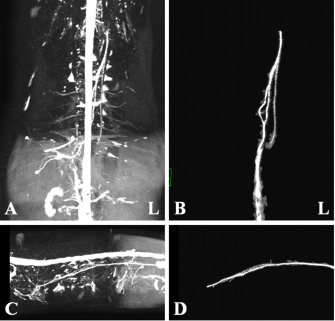

Fig. 1. Maximum intensity projection imaging of magnetic resonance thoracic ductography (MRTD). Cerebrospinal fluid, pleura, and kidney (renal pelvis) are shown (A, C). Unnecessary fluids were removed to construct the 3D image of MRTD (B, D). (A) Unprocessed MRTD image of the dorsal plane. (B) Processed MRTD image of the dorsal plane. (C) unprocessed MRTD image of the sagittal plane. (D) Processed MRTD image of the sagittal plane.

The raw MRI and CT data were transferred to a workstation (VAZE: PetCommunications, Chuo, Osaka, Japan) to construct the 3D images. In the MRTD images, the cerebrospinal fluid, pleura, kidney (renal pelvis) (Fig. 1A and C), part of the vessels (caudal vena cava, hepatic vein, and portal vein), and gastric juice were shown. Unnecessary fluids were removed in the maximum intensity projection (MIP) imaging of MRTD (Fig. 1B and D). Furthermore, 3D image of the thoracic duct was reconstructed from MRTD images, and 3D images of bone, heart, vessel, and esophagus were reconstructed from CT images. Those images were superposed using the “fusion” function on the workstation. The cerebrospinal fluid, kidney (renal pelvis), aorta, and liver vein (hepatic vein and portal vein) were used as indices of the superpose methods (Fig. 2A–C). The number of thoracic ducts at each vertebra between C5 andL2 were recorded in transverse MRTD (Fig. 2C) and T2WI (Fig. 2D). Location in relation to aorta and the location of the branches of thoracic duct were noted where possible. The comparison of the number of thoracic ducts at each vertebra between transverse T2WI and MRTD was performed using Student’s t-test. Statistical significance was set at p < 0.05.